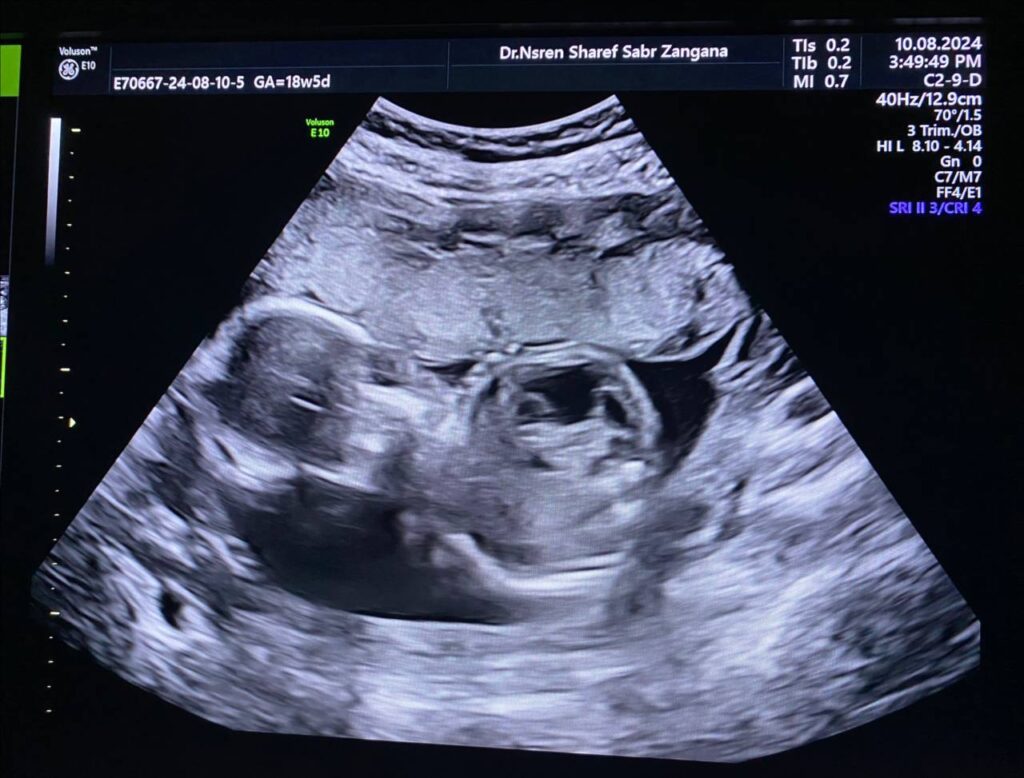

Same fetus when become about 19weeks

Right kidney enlarge in size 34x21x29mm, occupy by numerous

cysts of variable sizes, the largest 13mm , normal left kidney , polycystic ?